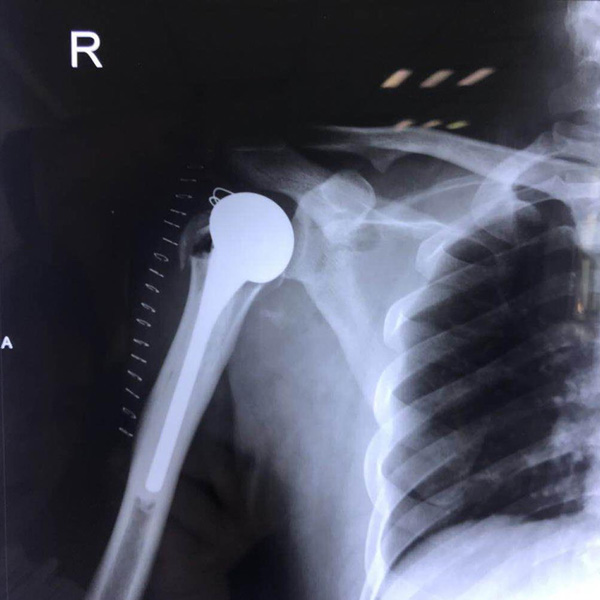

右側(cè)肱骨頭置換

患者郭某,男,40歲,因嚴(yán)重車禍導(dǎo)致“右肱骨頭粉碎性骨折”,一般的手術(shù)很難將粉碎的骨折塊拼接起來,即便大致的拼接起來,因為骨面的不平......